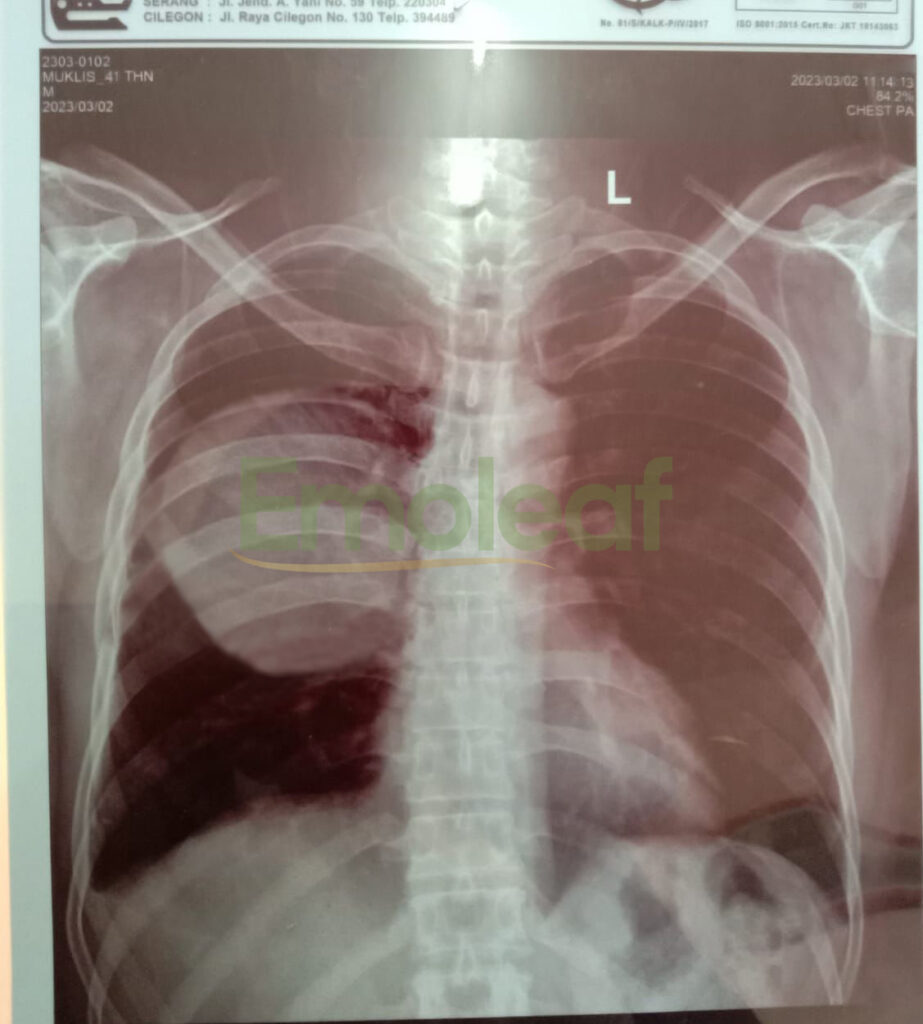

Sebelum Konsumsi Terapi Herbal

Maret 2023, tubuh saya mulai menunjukkan gejala berat seperti batuk disertai darah yang berkepanjangan, nyeri di dada hingga sesak napas. Sampai sempat masuk ICU, opname 1 minggu dan menggunakan oksigen karena sesak napas yang sudah tidak tertahan.

Hasil pemeriksaan menunjukkan saya terkena kanker paru dengan massa mencapai 4,2 cm. Direkomendasikan operasi, tapi keluarga saya tidak setuju, sehingga hanya dilakukan tindakan torakosentesis (sedot cairan di paru).

Hasil Rontgen Paru (16 April 2022)